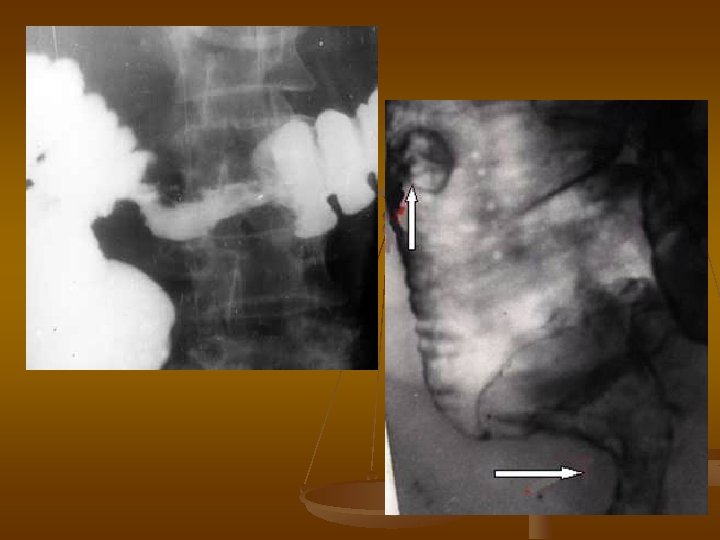

Преддивертикулярная стадия дивертикулярной болезни - спастический синдром. Поперечная исчерченность на пневморельефе в сочетании с о спикулообразными выпячиваниями по контурам сигмовидной кишки- рентгенологический симптом «частокола» . Сочетание преддивертикулярной стадии в нисходящей кишке (горизонтальная стрелка), стадии интрамуральных дивертикулов (вертикальная стрелка) и полных дивертикулов (фигурная стрелка).

Стадия полных дивертикулов. Множественные дивертикулы нисходящей кишки. Сочетание интрамурального (вертикальная стрелка) и полных дивертикулов в виде кольцевидной тени (горизонтальная стрелки) и дополнительной тени (фигурная стрелка).